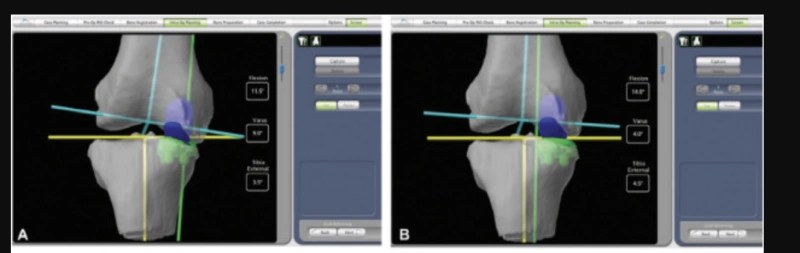

For Lindsey Vonn, surgeons planned an individual reconstruction tailored to the extreme demands of elite downhill skiing. Using high-resolution CT 3D scans, they were able to move beyond standardised, “one-size-fits-all” knee replacement, capturing the exact shape, density, and structure of her knee, including areas altered by years of injury and previous surgery.

Based on those scans, a digital twin model of Vonn’s knee was created, mapping the joint’s exact geometry, alignment, and rotational axes (the path along which force travels from the hip to the ankle). It allowed surgeons to analyse how her knee actually functioned rather than relying on population averages. The doctors had to assess varus (bow legs) and valgus (knocked knees) alignment, as well as the tibial slope (the angle of the top surface of the tibia relative to the horizontal), to determine how her knee was angled and tilted. They also had to identify subtle asymmetries that would be invisible on standard imaging but become critical under the high load. This level of precision was crucial, as even a one-degree misalignment can significantly overload cartilage and implants, especially under the extreme forces experienced in downhill skiing.

3D CT-based model individually designed to optimize implant placement in the sagittal, transverse and coronal planes. Photo credit to Strykier Mako Robotics

Finally, in the guided robot-assisted surgery, which translated digital planning into physical reconstruction with sub-millimetre accuracy, the personalised implant was placed. We must remember that the robotic system does not replace the surgeon. It rather prevents errors, ensuring bone cuts and implant placement remain within a tightly defined biomechanical boundaries that allow the knee to function safely with complete stability under load.